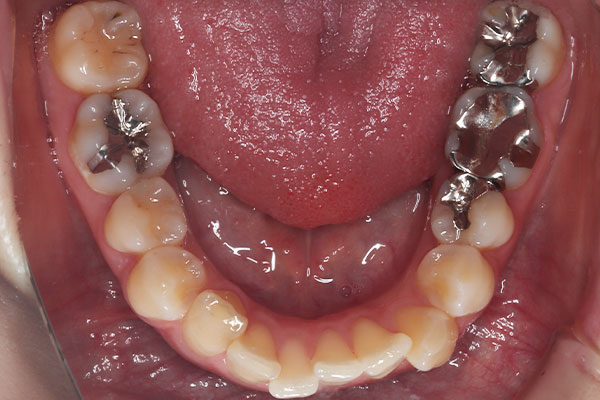

上下の前歯のガタガタを気にされて来院されました。

インビザラインライトにて改善しました。

治療前

治療後